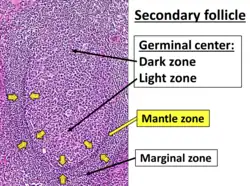

MCL is a subtype of B-cell lymphoma, due to CD5 positive antigen-naive pregerminal center B-cell within the mantle zone that surrounds normal germinal center follicles. MCL cells generally over-express cyclin D1 due to the t(11:14) translocation,[6] a chromosomal translocation in the DNA.

The history and physical examination may reveal some of the signs and symptoms consistent with Mantle Cell Lymphoma. Biopsy of the involved tissues (such as the lymph nodes, bone marrow, gastrointestinal tract, spleen or other areas) shows the characteristic histopathologic changes of MCL. There are distinct growth patterns of MCL seen on biopsy; these include the diffuse type, nodular type, mantle zone lymphoma and in situ mantle cell lymphoma.[7] In the diffuse growth pattern, there is a diffuse growth of lymphoma cells throughout the lymph node resulting in effacement of the architecture of the lymph node.[7] In the nodular type, there are large nodules of MCL cells in the lymph node with no germinal centers observed.[7] In MCL with expansion of the mantle zone, the lymphoma cells cause expansion of the mantle zone around normal germinal centers.[7] And in MCL in situ, the lymphoma cells are contained within the mantle zone without expansion.[7] Histologically, the lymphoma cells in classic MCL are characterized as small to medium lymphocytes with scant cytoplasm and clumped chromatin with prominent nuclear clefts and the nucleoli are not visible.[7] There are cytologic subtypes; the blastoid subtype, is characterized by round nuclei, fine chromatin with some distinct nucleoli.[7] The pleomorphic subtype is characterized by nuclei that vary in size and shape with some having a cleaved form.[7] The blastoid and pleomorphic subtypes of MCL are associated with a more aggressive course.[7]

The most common B-cell type seen in MCL is a pre-germinal center cell (that has not yet undergone the germinal center reaction), that is CD5, CD20, CD19 positive with expression of IgM and IgD with monoclonal kappa and gamma light chains.[18] CD23 and CD200 are usually negative and cyclin-D1 (a cell cycle regulatory protein controlling transition from the G1 phase to the S phase in the cell cycle) is classically overexpressed in MCL.[18] SOX11 (a transcription factor controlling genes involved in cell survival) is characteristically over-expressed in MCL as well.[18] Ki-67, a marker of cell proliferation, if elevated (greater than 30% expression) is associated with an aggressive course of MCL.[18]